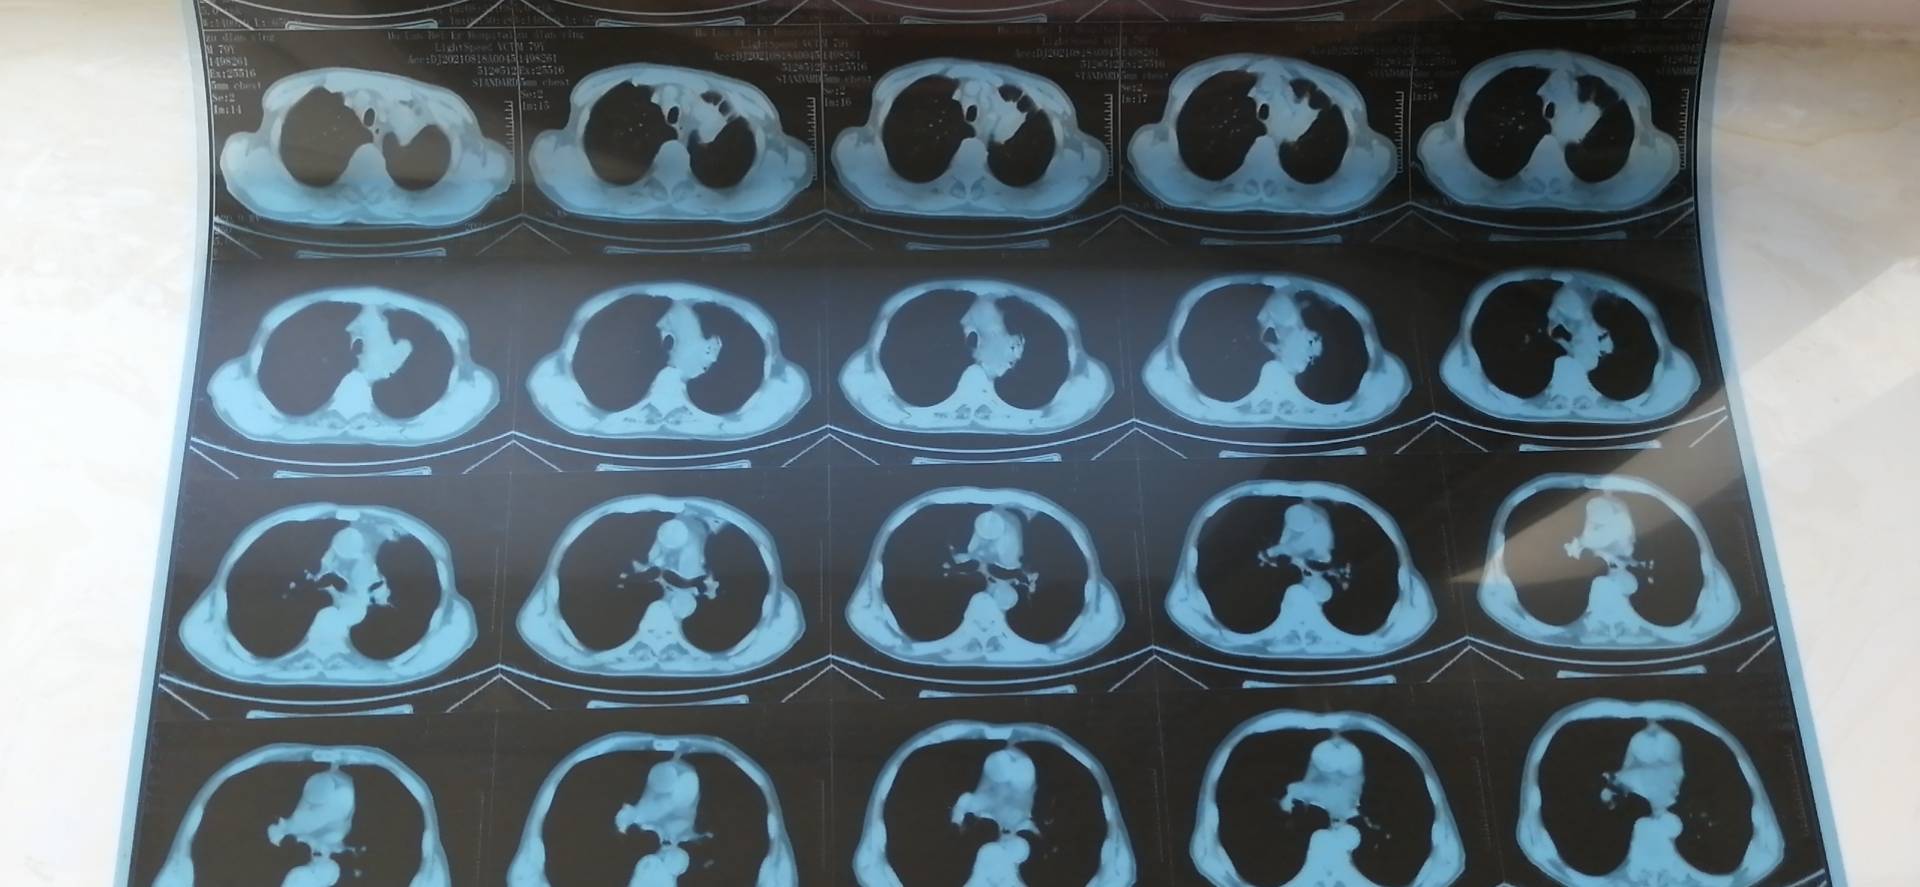

六次化疗加免疫结束了,第一天出各种血检结果,忐忑地站在自助机前打各种报告单,各种结果显示比上次检查结果要好,肿标各项停止了连升,都回到了正常值。第二天打ct胶片,腿还是控制不住地抖,但心里劝自己说第一天的血检结果都很好,这个也应该不会差。一张张胶片缓缓输出来,自己的心跳也越来越快,报告打出来的瞬间,自己冷静了一下才去看它。“4.7*2.6”,没敢相信自己的眼睛,又认真看了一遍的确是,心里的狂喜已经无法自制了。两年前确诊的时候是4.6*6,后期发展出现肺不张之后已经连成了一片白,最近一年的ct都已经不报肿瘤大小了。

感觉自己是一路小跑去找医生的,在医生那得到了肯定的结果:肿瘤缩小大半,胸腔积液消失,效果非常棒,下次撤掉化疗药,单免疫。

图片

治疗前后对比